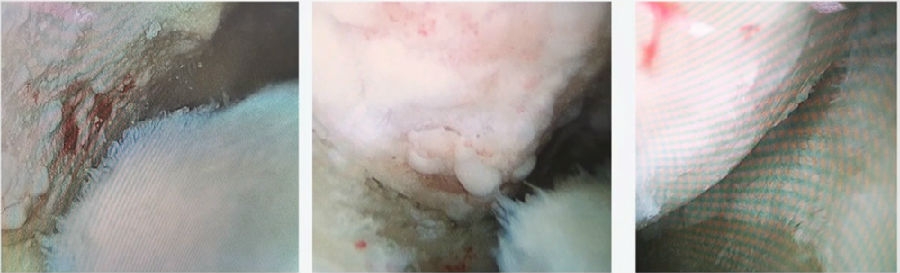

④术中首先关节镜探查。关节镜下软骨损伤3度,软骨脱落,软骨下骨暴露。

关节镜下所示

⑤同时做微骨折处理。

微骨折处理